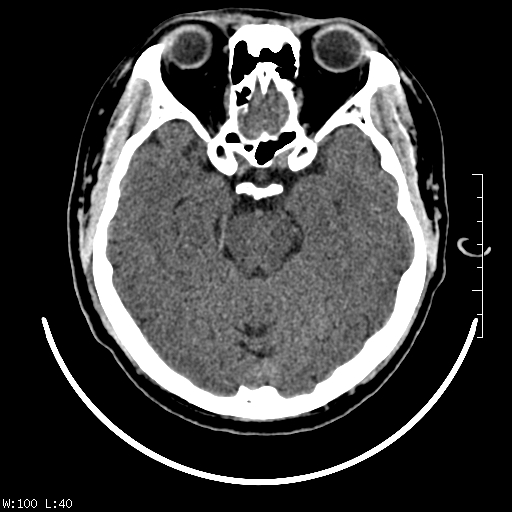

标题: CT22236:男,45,经常头痛。看看脑干正常吗? [打印本页]

标题: CT22236:男,45,经常头痛。看看脑干正常吗?

未见明显异常,建议ct增强或mri检查。

没见异常密度及形态改变啊,我认为是正常的。

颅脑ct轴位平扫颅内未见明确异常。

颅脑ct平扫未见明确异常,必要时mri检查。

颅脑ct平扫未见异常